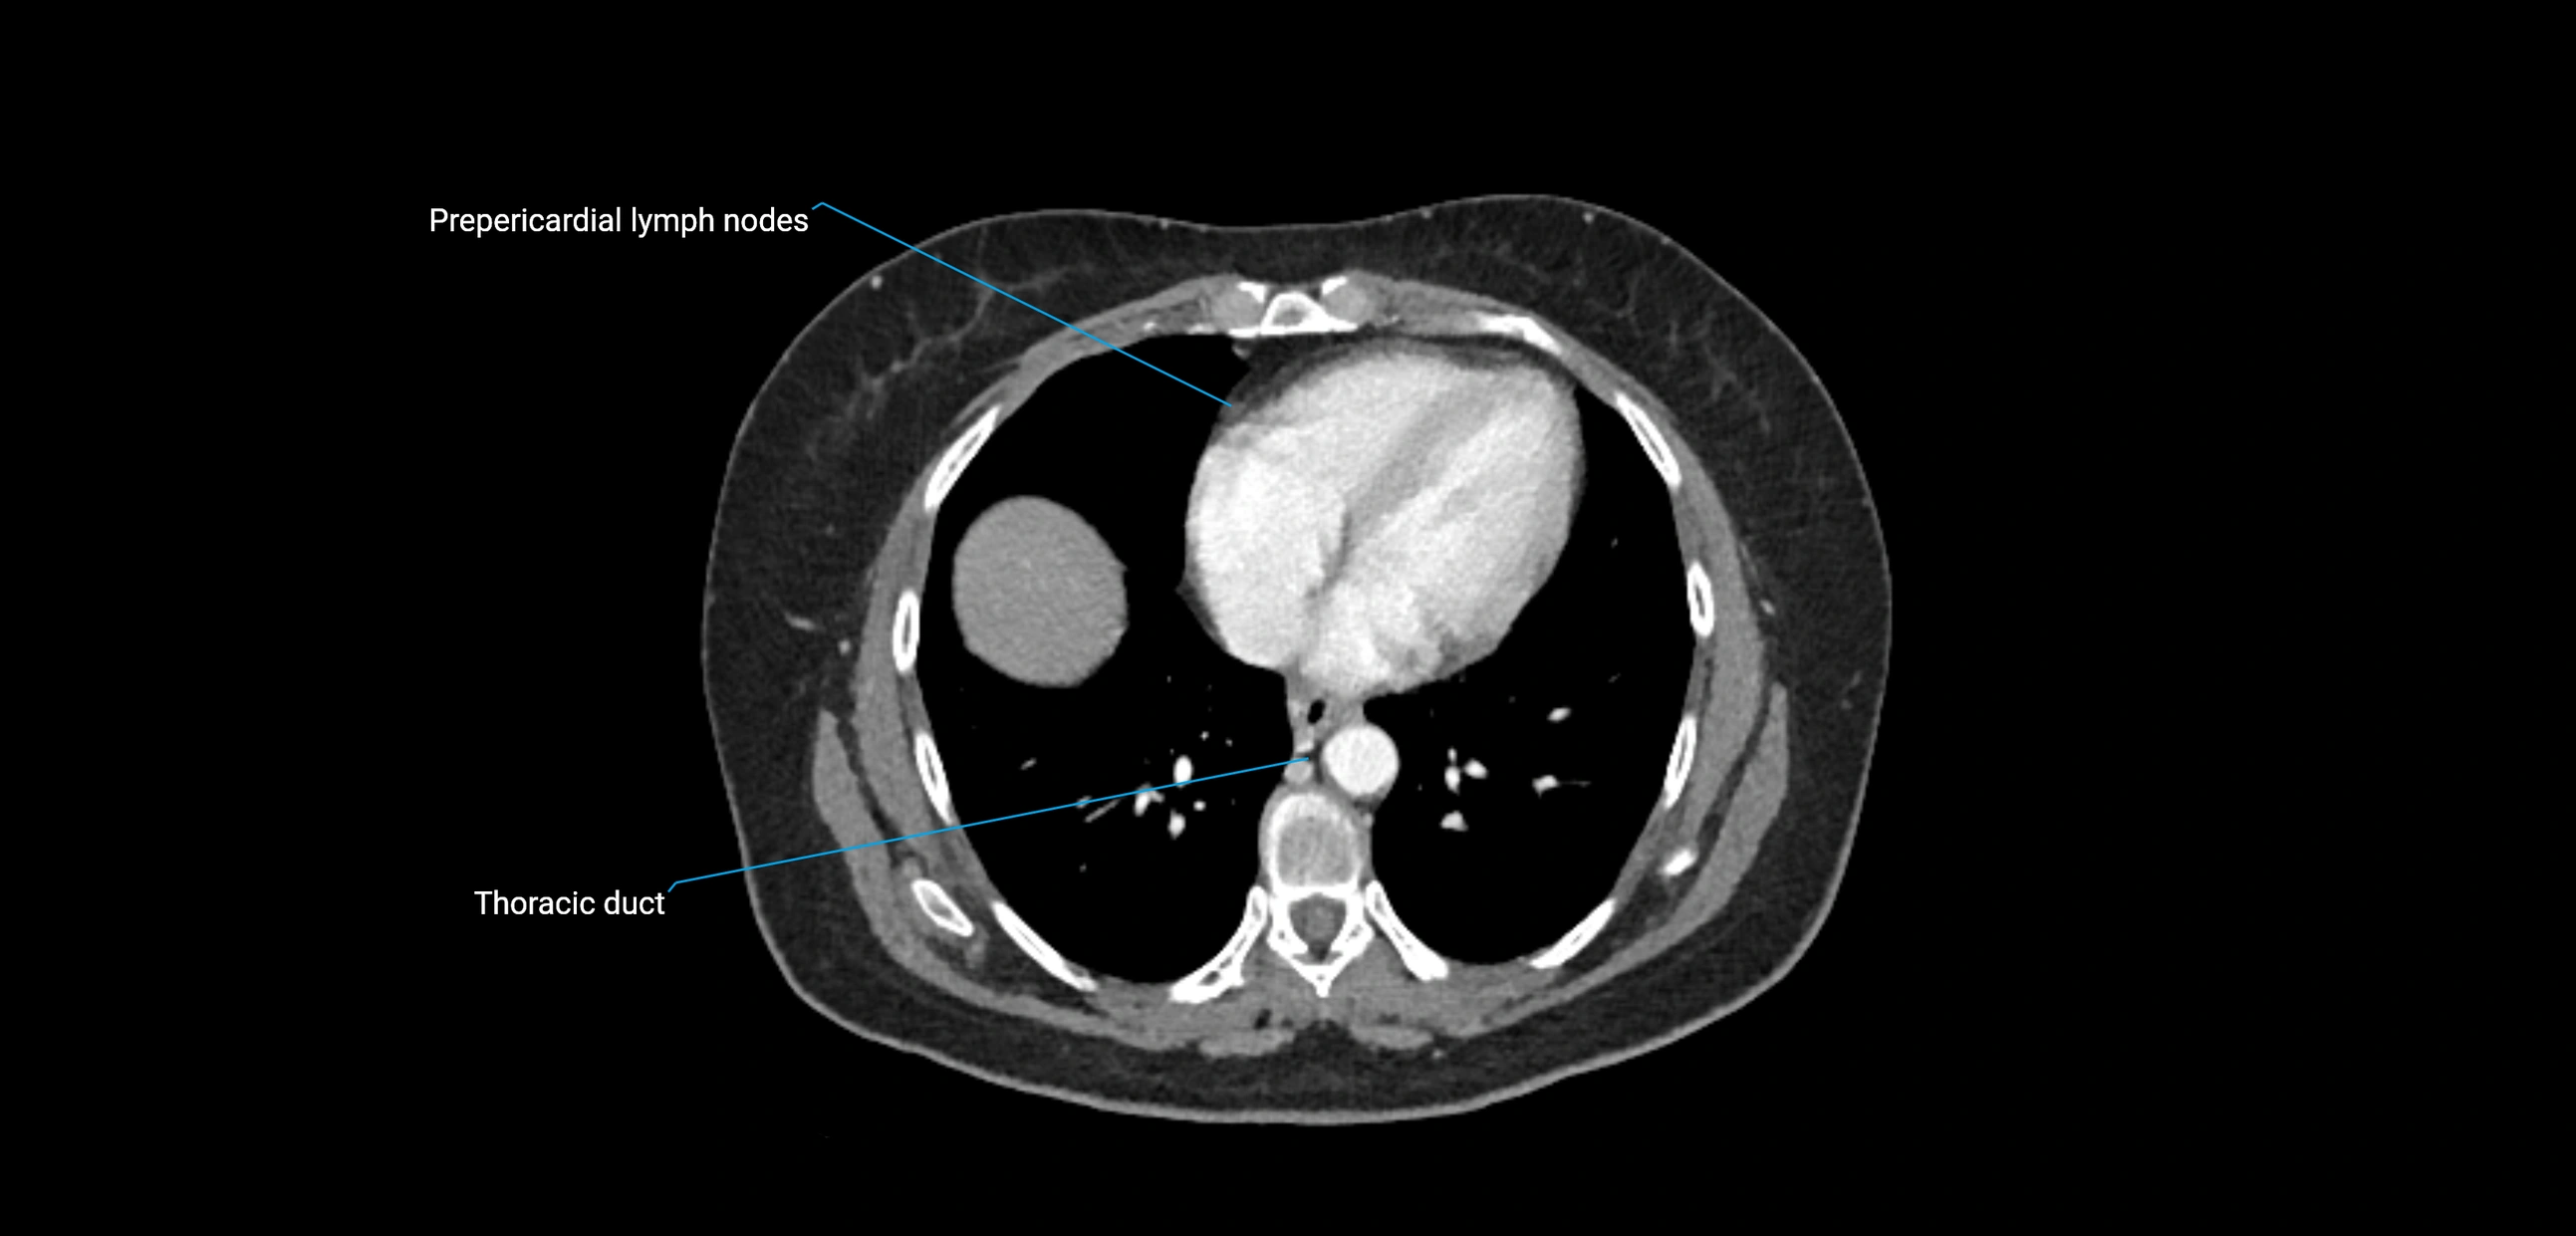

These nodes receive lymph from a wide range of abdominal and pelvic structures. Specifically, they drain lymph from the kidneys, suprarenal glands, gonads (testes/ovaries), uterus, uterine tubes, and pelvic organs, before converging into the lumbar lymphatic trunks, which terminate in the cisterna chyli → thoracic duct.

• Provide a major pathway to the cisterna chyli and thoracic duct